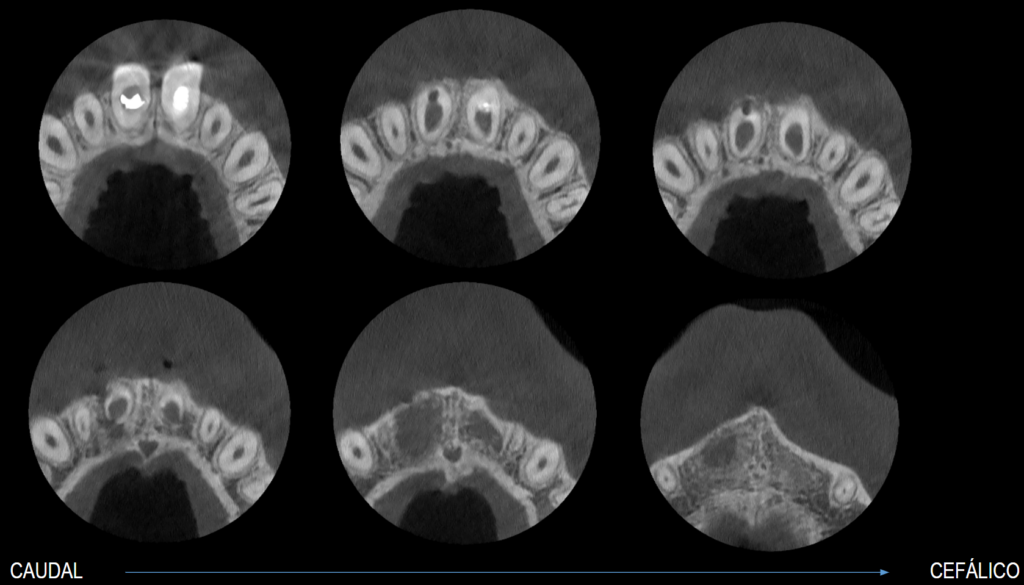

En la tomografía computarizada de haz cónico (CBCT) de campo reducido, evaluada en cortes axiales (Figura 2), coronales (Figura 3) y transaxiales (Figuras 4 y 5), se observa formación radicular incompleta, caracterizada por un conducto radicular amplio en los tercios medio y apical, así como un foramen apical de gran diámetro, asociado a un proceso osteolítico periapical difuso.

Adicionalmente, en la pieza 11 se identifica una imagen hipodensa de morfología tubular que se extiende desde el tercio cervical radicular hasta la superficie vestibular, provocando la pérdida de continuidad de la pared radicular, compatible con una perforación radicular iatrogénica. Se observa también pérdida de continuidad de la corona protésica, presencia de espigo-muñón y obturación

endodóntica del conducto.

CORTES AXIALES